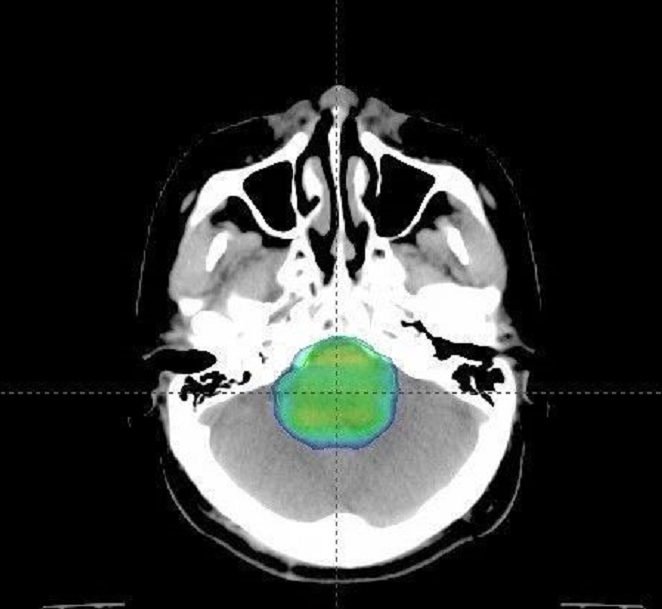

质子治疗剂量分布:质子治疗剂量分布均匀,对周围脑组织照射范围小